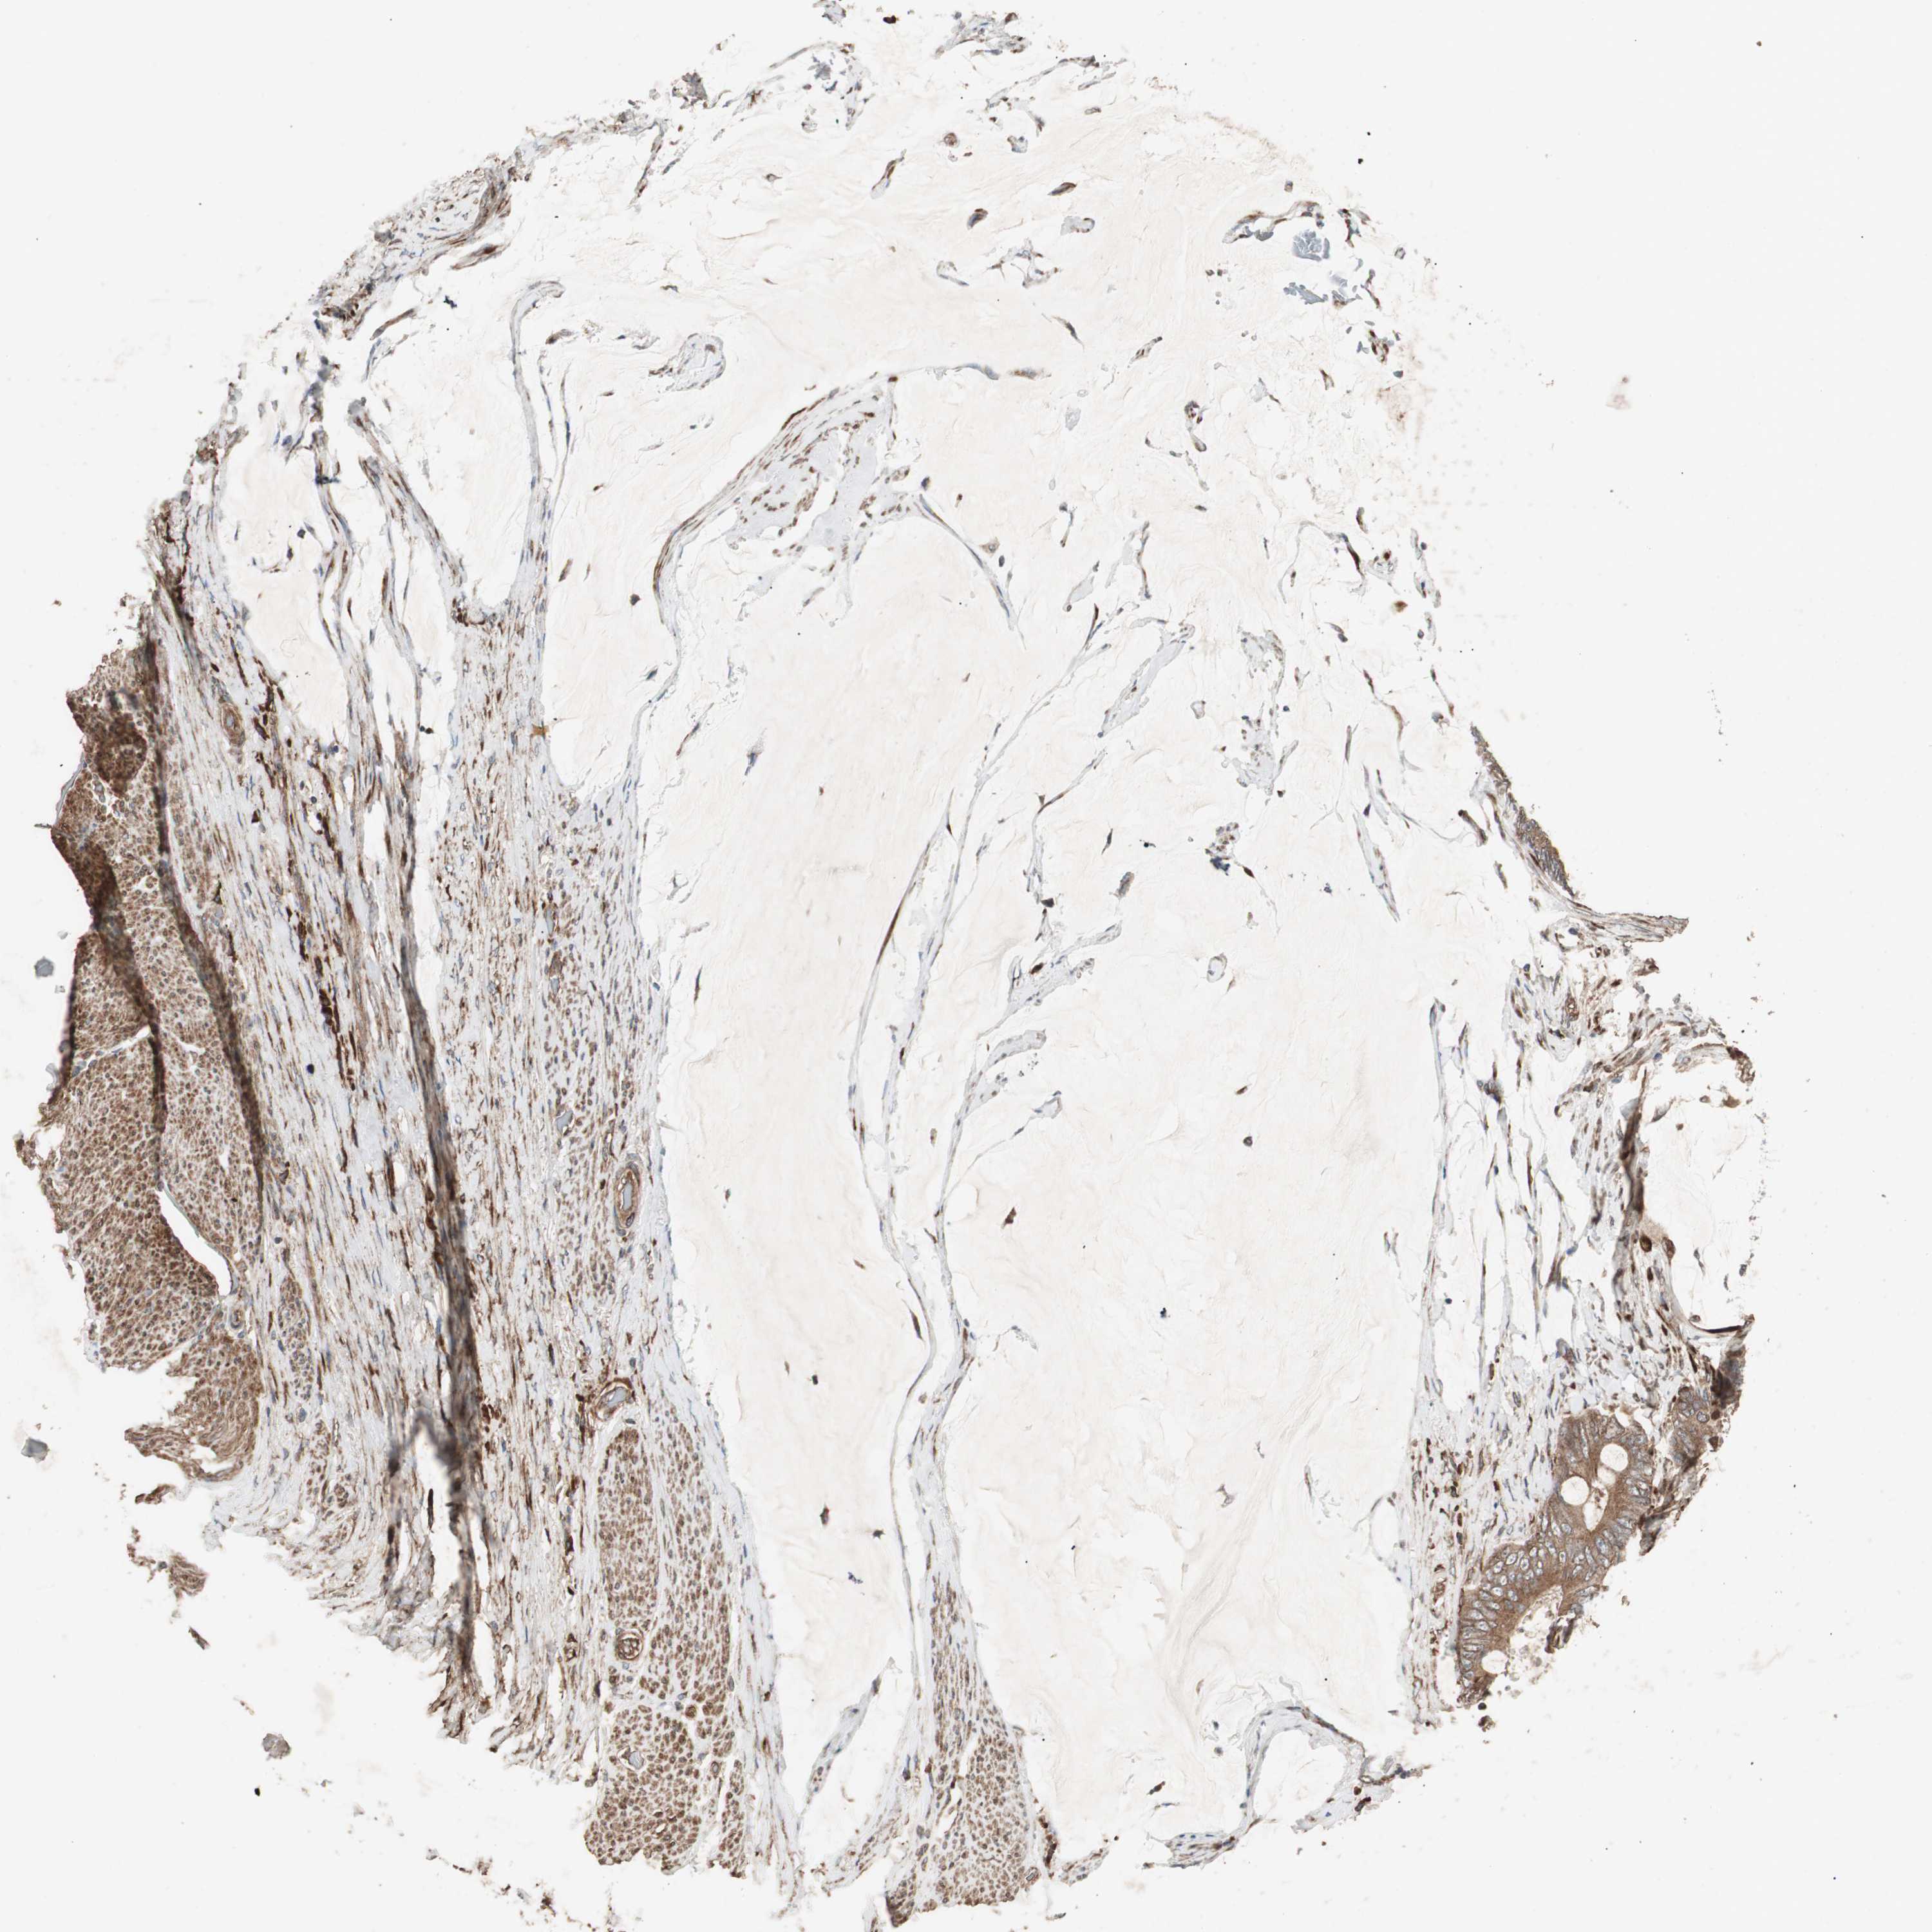

CANCER COLORECTAL CANCER Show tissue menu

Colorectal cancer

Human cancer

Colon adenocarcinoma